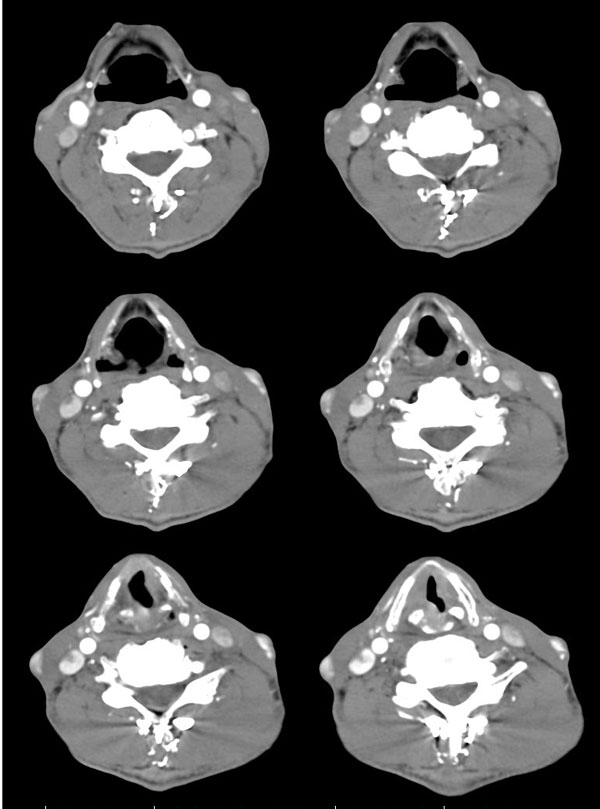

| 男性,57岁。反复声嘶1年,加重半年。 体检:喉粘膜充血,会厌肿胀,上举差,喉室及双声带窥视欠清。              蚂蚁发言:考虑喉癌(声门型)?双侧颈鞘周围淋巴结转移? 徐飞发言:有无呛水?根据病史要考虑球麻痹,脑干应检查 弯三角发言:考虑喉结核,应检查其它部位有无结核 卜一发言:喉腔右侧壁弥漫性软组织增厚,喉腔变窄。支持:喉癌(声门型)!另:双侧颈部多枚淋巴结肿大! 结果: 支纤镜检查:会厌板肿胀,右会厌咽侧壁肿胀,右杓状小结见结节样肿物,喉室肿胀,双声带肿胀、充血,左声带见菜花样肿物,触及易出血,取活检。 病理诊断:高分化鳞状细胞癌。 免疫组化:ck(h)(+++)、pcna(++)、p53(++)、ck(l)(-)。 原贴地址:http://www.radinet.com.cn/forum_view.asp?forum_id=4&view_id=34703 |